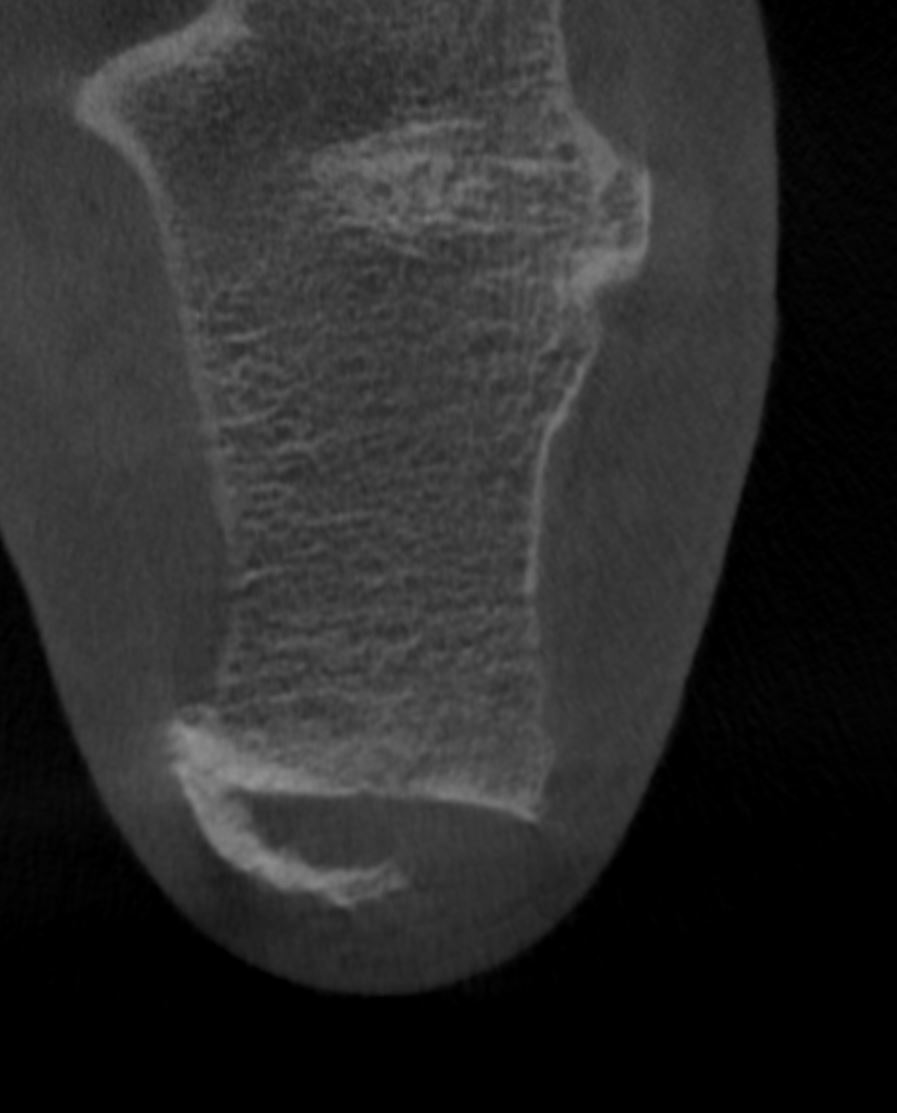

Home Schwerpunkte Krankheitsbilder Haglund-Syndrom & Haglundferse Haglund Ferse und dorsaler Fersensporn vor der OP

Haglund Ferse und dorsaler Fersensporn vor der OP